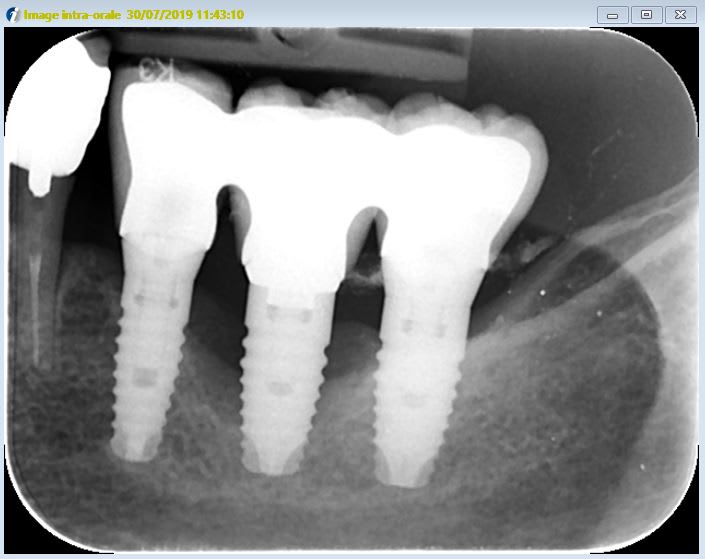

Bonjour je pense que ce sont des implants TBR mais je n'en suis pas sûr.

qu'en pensez-vous?

qu'il y a des excès de ciment +++

Non, ce sont des particules de métal qui n'ont pas encore été rincées suite à la réalisation de puits d’accès occlusaux pour démontage et explantation de l'implant 36....

çà ressemble fort à du TBR Conic